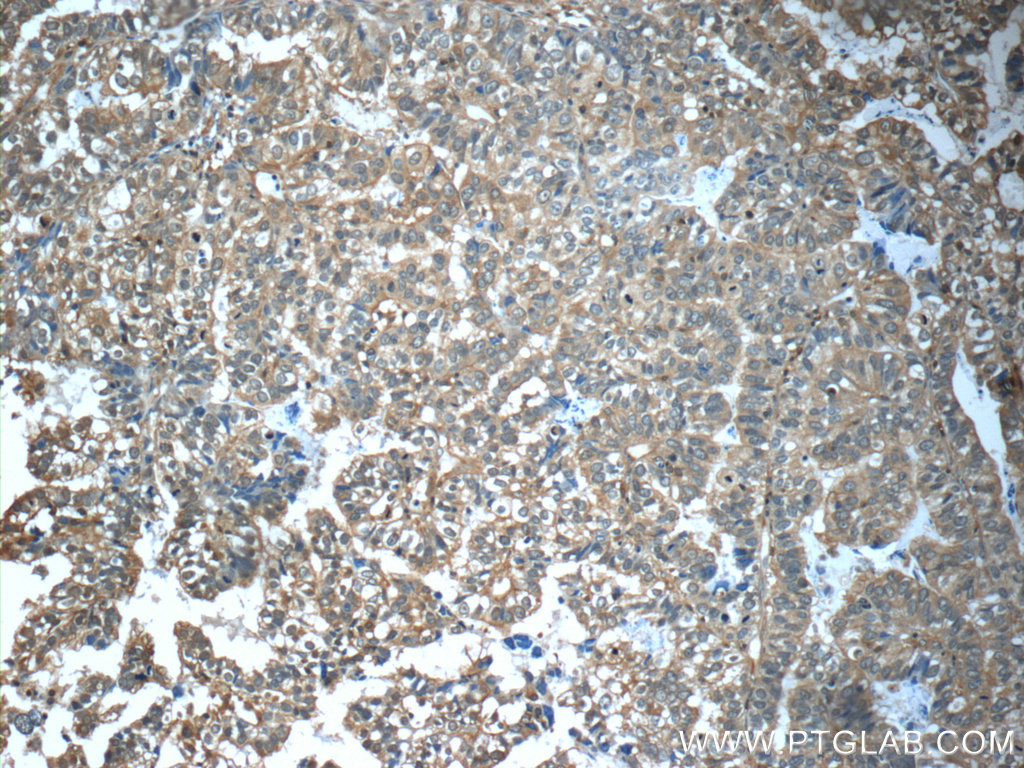

- Immunohistochemistry of paraffin-embedded human breast cancer tissue slide using 20738-1-AP( CFTR Antibody) at dilution of 1:50 (under 10x lens)

- Other comments

- IHC

- The CFTR antibody from Proteintech is a rabbit polyclonal antibody to a peptide of human CFTR. This antibody recognizes human antigen. The CFTR antibody has been validated for the following applications: ELISA, IHC analysis.